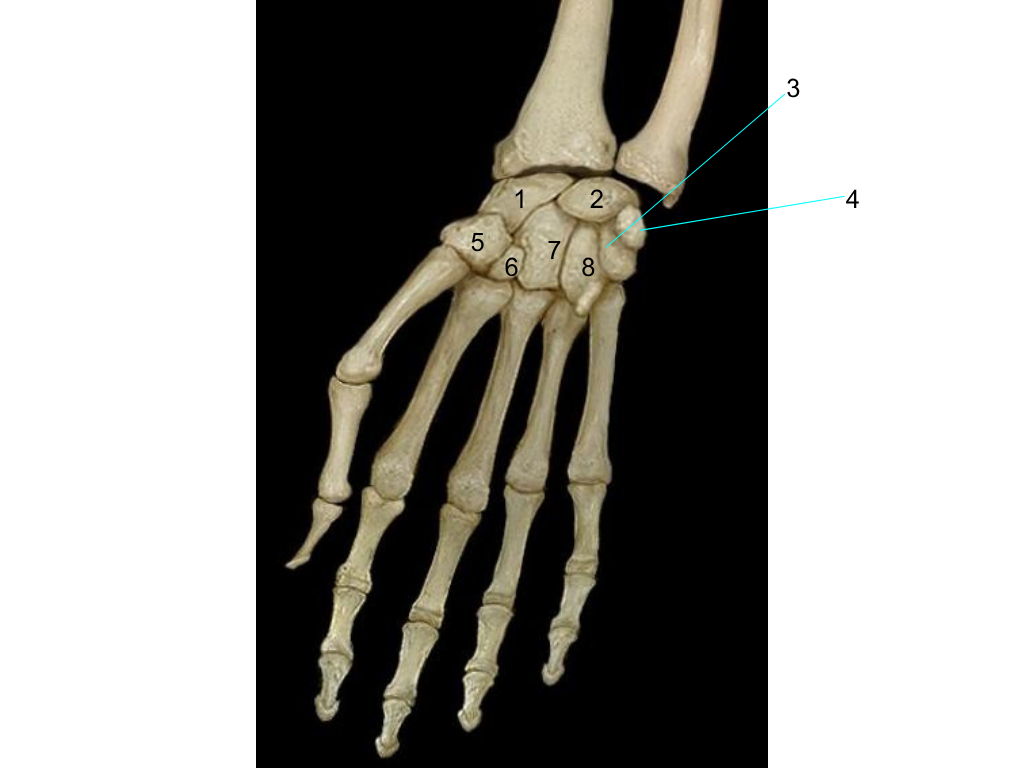

scaphoid

what is #1 pointing at?

lunate

what is #2 pointing at?

triquetrum

what is #3 pointing at?

quisiform

what is #4 pointing at?

trapezium

what is #5 pointing at?

trapezoid

what is #6 pointing at?

capitate

what is #7 pointing at?

hamate

what is #8 pointing at?

metacarpals

proximal phalanges

middle phalanges

distal phalanges